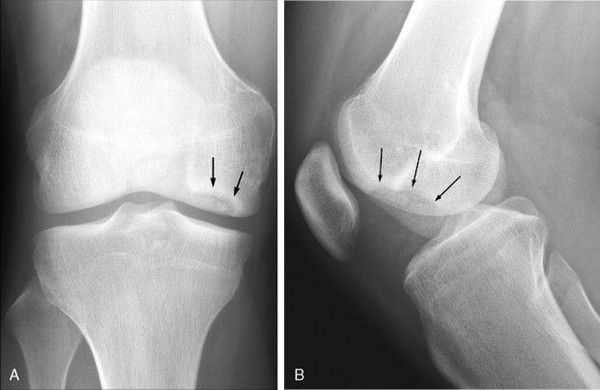

Основным методом инструментальной диагностики является рентген коленных суставов в двух проекциях, который позволяет увидеть структурные изменения бугристости [4] .

Фрагментацию с отрывом костного фрагмента лучше всего видно на боковой рентгенограмме [10] .

- острая стадия — края собственной связки надколенника становятся нечёткими из-за отёка мягких тканей, через 3–4 месяца бугристость меняет форму, а её омертвевшие участки начинают рассасываться;

- подострая стадия — отёк мягких тканей рассасывается, но изменения бугристости остаются;

- хроническая стадия — фрагмент кости может срастись с нормальной частью бугристости [13] .